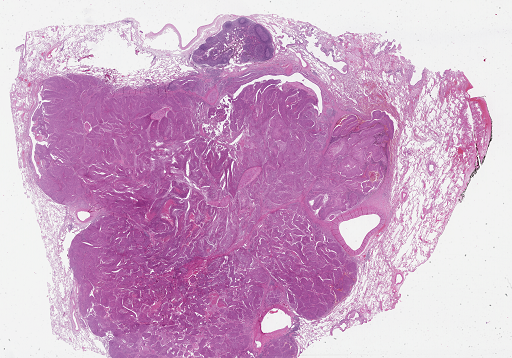

For qualitative ROI detection evaluation check Fig. 3.

Refer to caption

(a)

(b)

Figure 3: Qualitative view of ROIs recognized by Suffy through its Patch Classification. (a) An example WSI from the test set of the CAMELYON16 dataset [3]. (b) ROIs are identified by Snuffy with black lines delineating the ground truth ROIs.